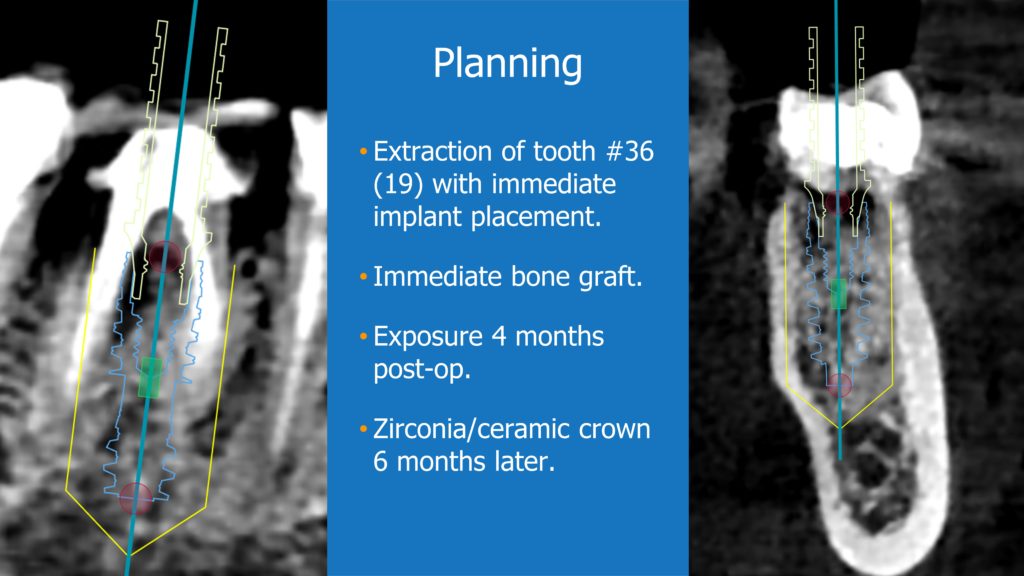

A healthy 36 year old woman comes to the clinic with pain and swelling in the area of the inferior left molars. In the intraoral observation, a vestibular fistula was identified, and the complementary exams confirmed a bone lesion caused by a root perforation (poorly executed false post) on the first lower left molar #36 (19). It was decided to do antibiotic therapy for a week and then the tooth extraction with immediate implant placement and bone graft. 4 months post-op the definitive zirconia/ceramic crown would be was made.